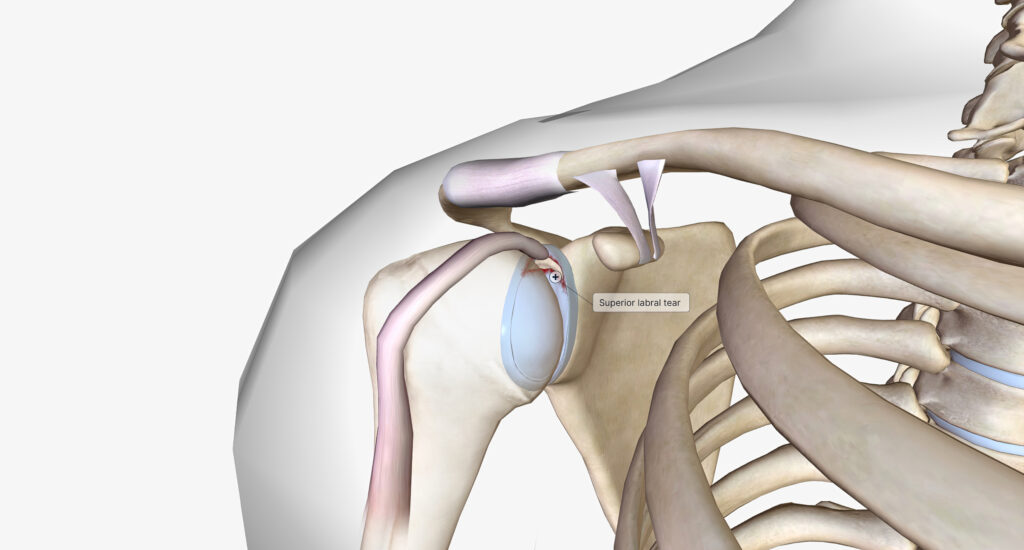

Shoulder instability occurs when the ball of the shoulder joint moves excessively or comes out of the socket. This may range from subtle instability to full dislocation.

Instability may be caused by:

- Traumatic injury, such as a fall or sporting collision

- Recurrent dislocations

- Damage to the labrum or joint capsule

- Congenital joint laxity in some individuals

Symptoms may include a feeling of the shoulder “giving way,” pain, apprehension with certain movements, or repeated dislocations. Recurrent instability can increase the risk of further soft tissue damage if left untreated.